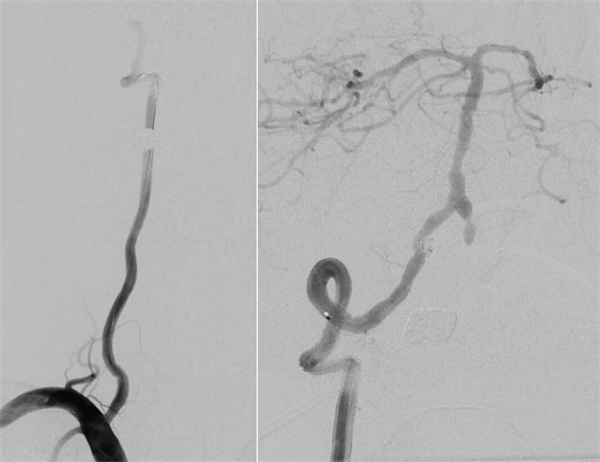

患者高先生,70岁,患有高血压病多年。2年前曾行冠状动脉搭桥术,平素规律服药。2个月前,他因左上肢突然麻木被送至清华大学垂杨柳医院急诊科就诊。头颅CT提示右侧顶叶少量蛛网膜下腔出血。后入住神经外科进一步诊治,全脑血管造影(DSA)结果显示:右侧椎动脉起始部重度狭窄约70%,左侧椎动脉颅内段闭塞;右侧椎动脉颅内段存在大小约3.5×2毫米的夹层动脉瘤;右侧颈内动脉颅外段存在重度狭窄,左侧颈内动脉通过前交通动脉代偿。

▲右侧椎动脉起始重度狭窄,左侧椎动脉颅内段闭塞

▲右侧椎动脉V4段夹层动脉瘤

第四步,最终验证。再次造影显示:狭窄消失,支架位置良好。动脉瘤不显影,弹簧圈致密填塞。